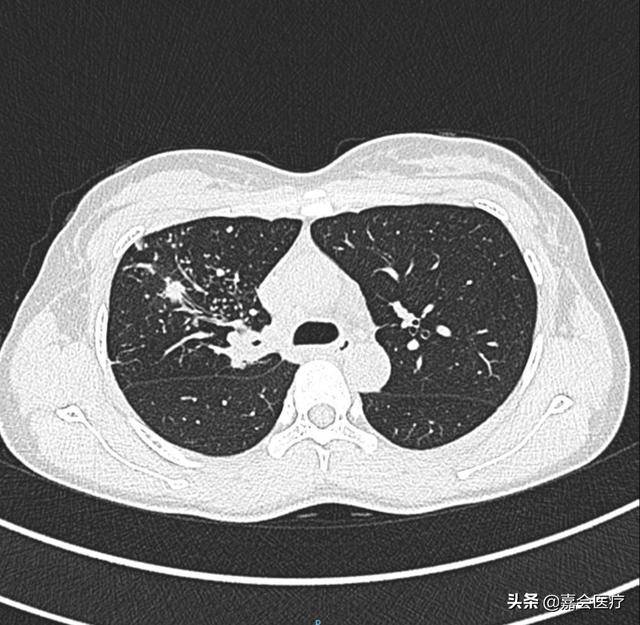

肺结核肺部ct表现,肺结核ct表现

而肺部ct(下图右)的敏感性要高于胸片,可以看到 典型的结核表现为结节